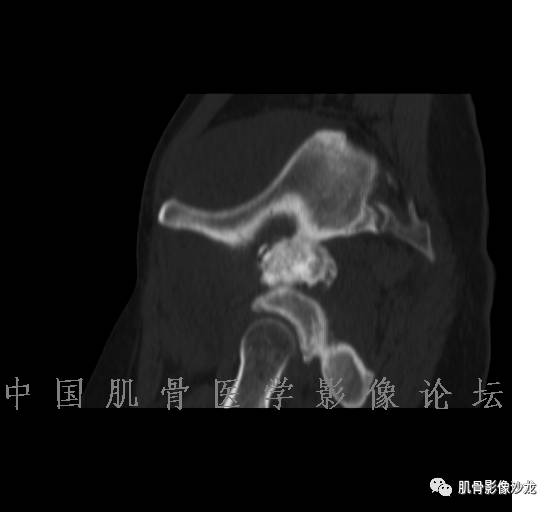

1、软骨肉瘤可以有膨胀性骨质破坏(病例3,4),可以有溶骨性骨质破坏(病例2),局部皮质因为破坏变薄,中断 ;

2、软骨基质T2WI高信号,软骨小叶分叶状,也就会出现高老师提到的骨内膜扇贝形压迹。一般认为骨内膜扇贝形压迹超过骨皮质厚度的2/3是软骨肉瘤在长管状骨的特征性表现。如上图。3、软组织肿块或肿胀;

4、 钙化,环形,弓形,边缘模糊 ;

5、增强后进行性延迟,不均匀分割状强化, 会强化的纤维间隔,软骨小叶不会强化,关于老师们说到的钙化,软骨肉瘤不一定会有钙化 。

雪舞 :1、骨恶性肿瘤的发病率排名:多发骨髓瘤、骨肉瘤和软骨肉瘤

2、软骨肉瘤的发病部位排名:最好发部位为髂骨,其次股骨、肱骨和脊柱。